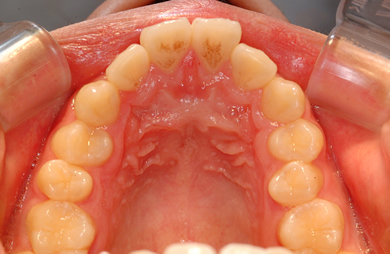

| 主訴 | 乱ぐい歯を治したい。 | ||||||||||||||||||||||||||||||||

| 治療方針 | 歯のがたつきが大きいことより上下左右第一小臼歯を抜歯して、マルチブラケット装置にて治療。また、親不知がまっすぐ生えることができず横を向いている状態なので、まっすぐにする隙間があることから親不知も使用し、矯正を行う。 | ||||||||||||||||||||||||||||||||

| 治療内容 | 唇側矯正(ホワイト) | ||||||||||||||||||||||||||||||||